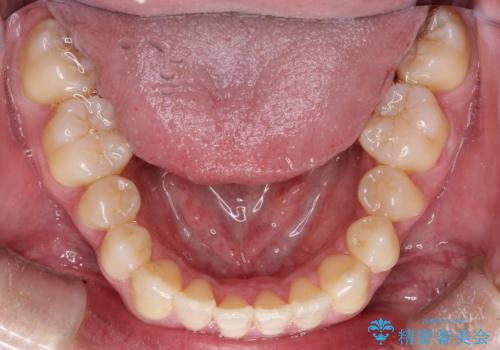

上下のがたつきをインビザラインで目立たない矯正

- 前歯のガタガタを主訴に来院されました。

上下の前歯のガタガタと左上の歯が反対にかんでいる状態でした。

上下の歯と歯の間をわずかに削り並べる計画としました。

目立たずに歯並びがよくなり、前歯に装着されたセラミックも壊さずに矯正治療が終了し満足していただけました。